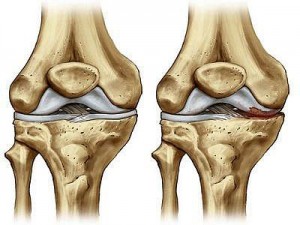

Oltre ai tendini e ai legamenti, il funzionamento del ginocchio è garantito dalla capsula sinoviale, una camera che si trova tra il femore e la tibia. I capi articolari sono ricoperti dalla cartilagine, che ha lo scopo di favorire il movimento dell’articolazione. Questa a sua volta, è protetta dalla presenza dei menischi. Questi hanno il ruolo di ammortizzare il carico che l’individuo esercita durante la vita quotidiana, o durante lo sport. Quando queste strutture si degradano, possono rompersi, causando difficoltà di movimento e crescente dolore. Nei casi di lesione traumatica del menisco, la procedura chirurgica spesso prevede l’asportazione della parte lesionata. In questo modo, però, si espone la cartilagine a traumi diretti che possono accelerarne l’erosione.

RISULTATI – La RMN non ha rilevato la presenza di formazione anomale di tessuto all’interno del ginocchio. I pazienti che avevano ricevuto una dose più alta hanno mostrato un incremento del volume meniscale di oltre il 15 per cento. Quelli con la dose minore del solo del sei per cento mentre il gruppo “placebo” non ha manifestato alcun miglioramento. Inoltre la sensazione dolorosa è diminuita di quattro punti su una scala di 10. I ricercatori hanno quindi potuto concludere che la somministrazione di cellule staminali mesenchimali può costituire un aiuto efficace e sicuro per i pazienti colpiti da forme di degenerazione delle cartilagini del ginocchio.